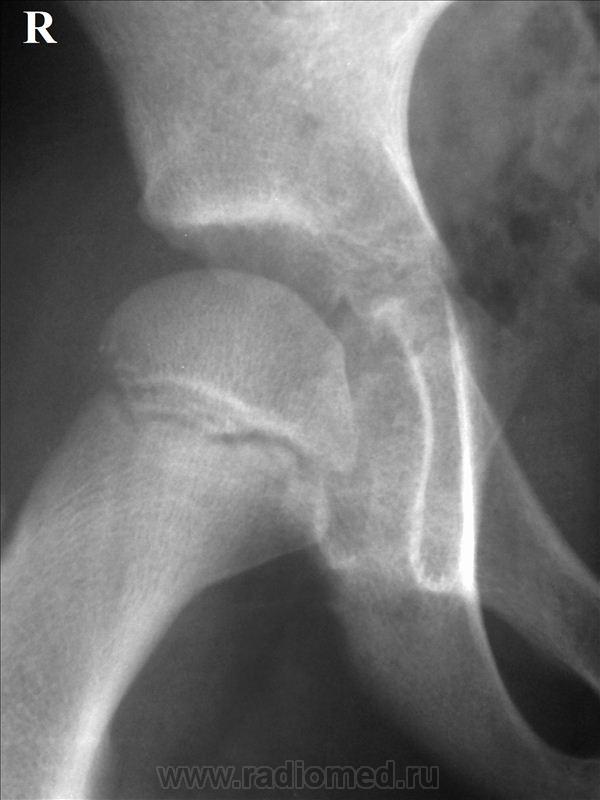

Случай по дежурству. Мальчик 8 лет. стал испытывать боль в правой нижней конечности около недели назад, несмотря на это продолжал активно заниматься футболом. Вчера боль в т\бедренном суставе резко усилились, появилось вынужденное положение, незначительная ротация бедра кнутри, и сгибание коленного сустава 175 гр, осевая нагрузка на нижнюю конечность не возможна из-за выраженного болевого синдрома, температура 37,4, в ОАК лейкоцитоз 13.4, палочки 9, СОЭ 28 мм\час. На рентгенограмме т\бедренных суставов мне не понравился медиальный участок суставной поверхности головки правого бедра. Можно ли данный случай считать начальным проявлением болезни Пертеса?

Александр Викторович, здравствуйте.Спасибо, что не выполнили обещание. Первое, на что обратила внимание-укорочение шейки левой бедренной кости,увеличение ШДУ( укладка, дисплазия?). Первая стадия болезни Пертеса рентгеннегативна.Цитирую И.А.Шехтера."Начальным рентгенологическим признаком является ф дальнейшем наступающее расширение рентгеновской суставной щели.Вторая стадия характеризуется наличием резко повышенной интенсивности тени эпифизарной головки, которая уменьшена в размерах, несколько деформирована и сплющена вследствие импрессионного перелома.Одновременно уже хорошо выявляется значительное расширение рентгеновской суставной щели.Почти как правило ,обнаруживается небольшой подвывих бедра, который остается на протяжении всего заболевания".Динамика нужна.Если есть клиника ( а я не сомневаюсь, что Вы замечательный клиницист), то , конечно,Вы все правильно делаете.Жду мнение уважаемых коллег.

Наверное, начальные проявления все-таки есть в виде небольшой деформации головки .Интересно, а кто-нибудь ставил первую-вторую стадии болезни Пертеса?Я чаще всего наблюдала уже исход.Как-то даже пациентка была из Белгорода, где ей упорно ставили ДОА.Приехала к родственнице-нашей коллеге.Мы ей Пертеса поставили, областные травматологи подтвердили, прооперировали.Женщина счастлива и довольна.Столько лет мучилась, а на Сахалине ей помогли.Вот хвастаюсь.

Думаю, что о болезни Пертеса говорить рано, явной деструкции и подвывихов нет, отмирать должны участки головки, контактирующие именно с крышей вертлужной падины. А здесь якобы страдает медиальная поверхность. Но обратите внимание - при сравнении с контрлатеральной головкой на снимках видны не симметричные участки, а другие, что обусловлено несимметричностью бедер, углы ротации бедер при снимке - не равны. Еще - есть явная рабочая гипертрофия внутренних полуцилиндров бедер, а шеечно - диафизарный угол слева - увеличен. Слева - легкая неоднородность в структурах шейки бедра, но возможно это остеопороз...

Лаунштейна бы, для полного счастья... Ибо ЮЭГБ не дремлет. А на Пертеса вроде бы не похоже.

Особенно если обратить внимание на структуру наружно-нижнего края эпифиза бедра справа, неравномерность щели между эпифизом и метафизом справа, легкую неконгруентность справа...да и футбол из той же оперы....

Я бы предположила юношеский остеоэпифизиолиз головки бедра, достаточно убедительная картинка.

Ни за болезнь Пертеса, ни за эпифизеолиз данных не вижу, скорее всего, у ребенка артрит. Хорошо бы УЗИ сустава.